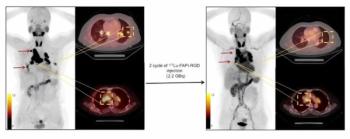

The dual-targeted 177Lu-DOTA-FAPI-RGD reportedly reduced or stopped the growth of cancer lesions in 88.9 percent of advanced adenocarcinomas in a small cohort of patients with varied cancers including pulmonary, pancreatic and ovarian cancer, according to new research presented at the SNMMI conference.